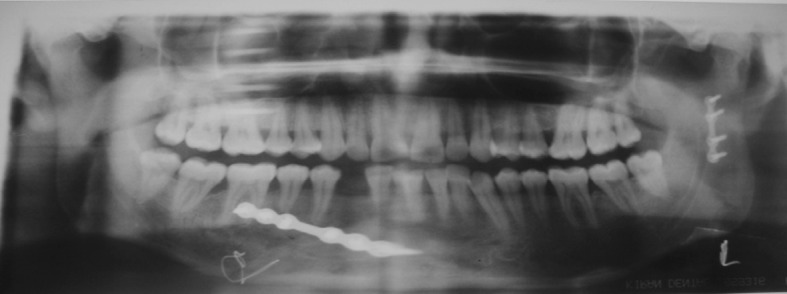

Fig. 10.

6 month post operative OPG

Radiographic examination revealed proper approximation of fracture fragments with good bone healing (Figs. 5 and 10), no evidence of plate exposure and screw loosening except in one case in preauricular approach. Sign of condylar resorption was seen in two cases after 3 months and complete resorption after 6 months in preauricular approach, whereas none in retromandibular approach (Figs. 1, 4, 6, and 9).